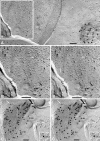

Aquaporin (AQP) water channels are abundant in the brain and spinal cord, where AQP1 and AQP4 are believed to play major roles in water metabolism and osmoregulation. Immunocytochemical analysis of the brain recently revealed that AQP4 has a highly polarized distribution, with marked expression in astrocyte end-feet that surround capillaries and form the glia limitans; however, the structural organization of AQP4 has remained unknown. In freeze-fracture replicas, astrocyte end-feet contain abundant square arrays of intramembrane particles that parallel the distribution of AQP4. To determine whether astrocyte and ependymocyte square arrays contain AQP4, we employed immunogold labeling of SDS-washed freeze-fracture replicas and stereoscopic confirmation of tissue binding. Antibodies to AQP4 directly labeled approximately 33% of square arrays in astrocyte and ependymocyte plasma membranes in rat brain and spinal cord. Overall, 84% of labels were present beneath square arrays; 11% were beneath particle clusters that resembled square arrays that had been altered during fixation or cleaving; and 5% were beneath the much larger areas of glial plasma membrane that were devoid of square arrays. Based on this evidence that AQP4 is concentrated in glial square arrays, freeze-fracture methods may now provide biophysical insights regarding neuropathological states in which abnormal fluid shifts are accompanied by alterations in the aggregation state or the molecular architecture of square arrays.